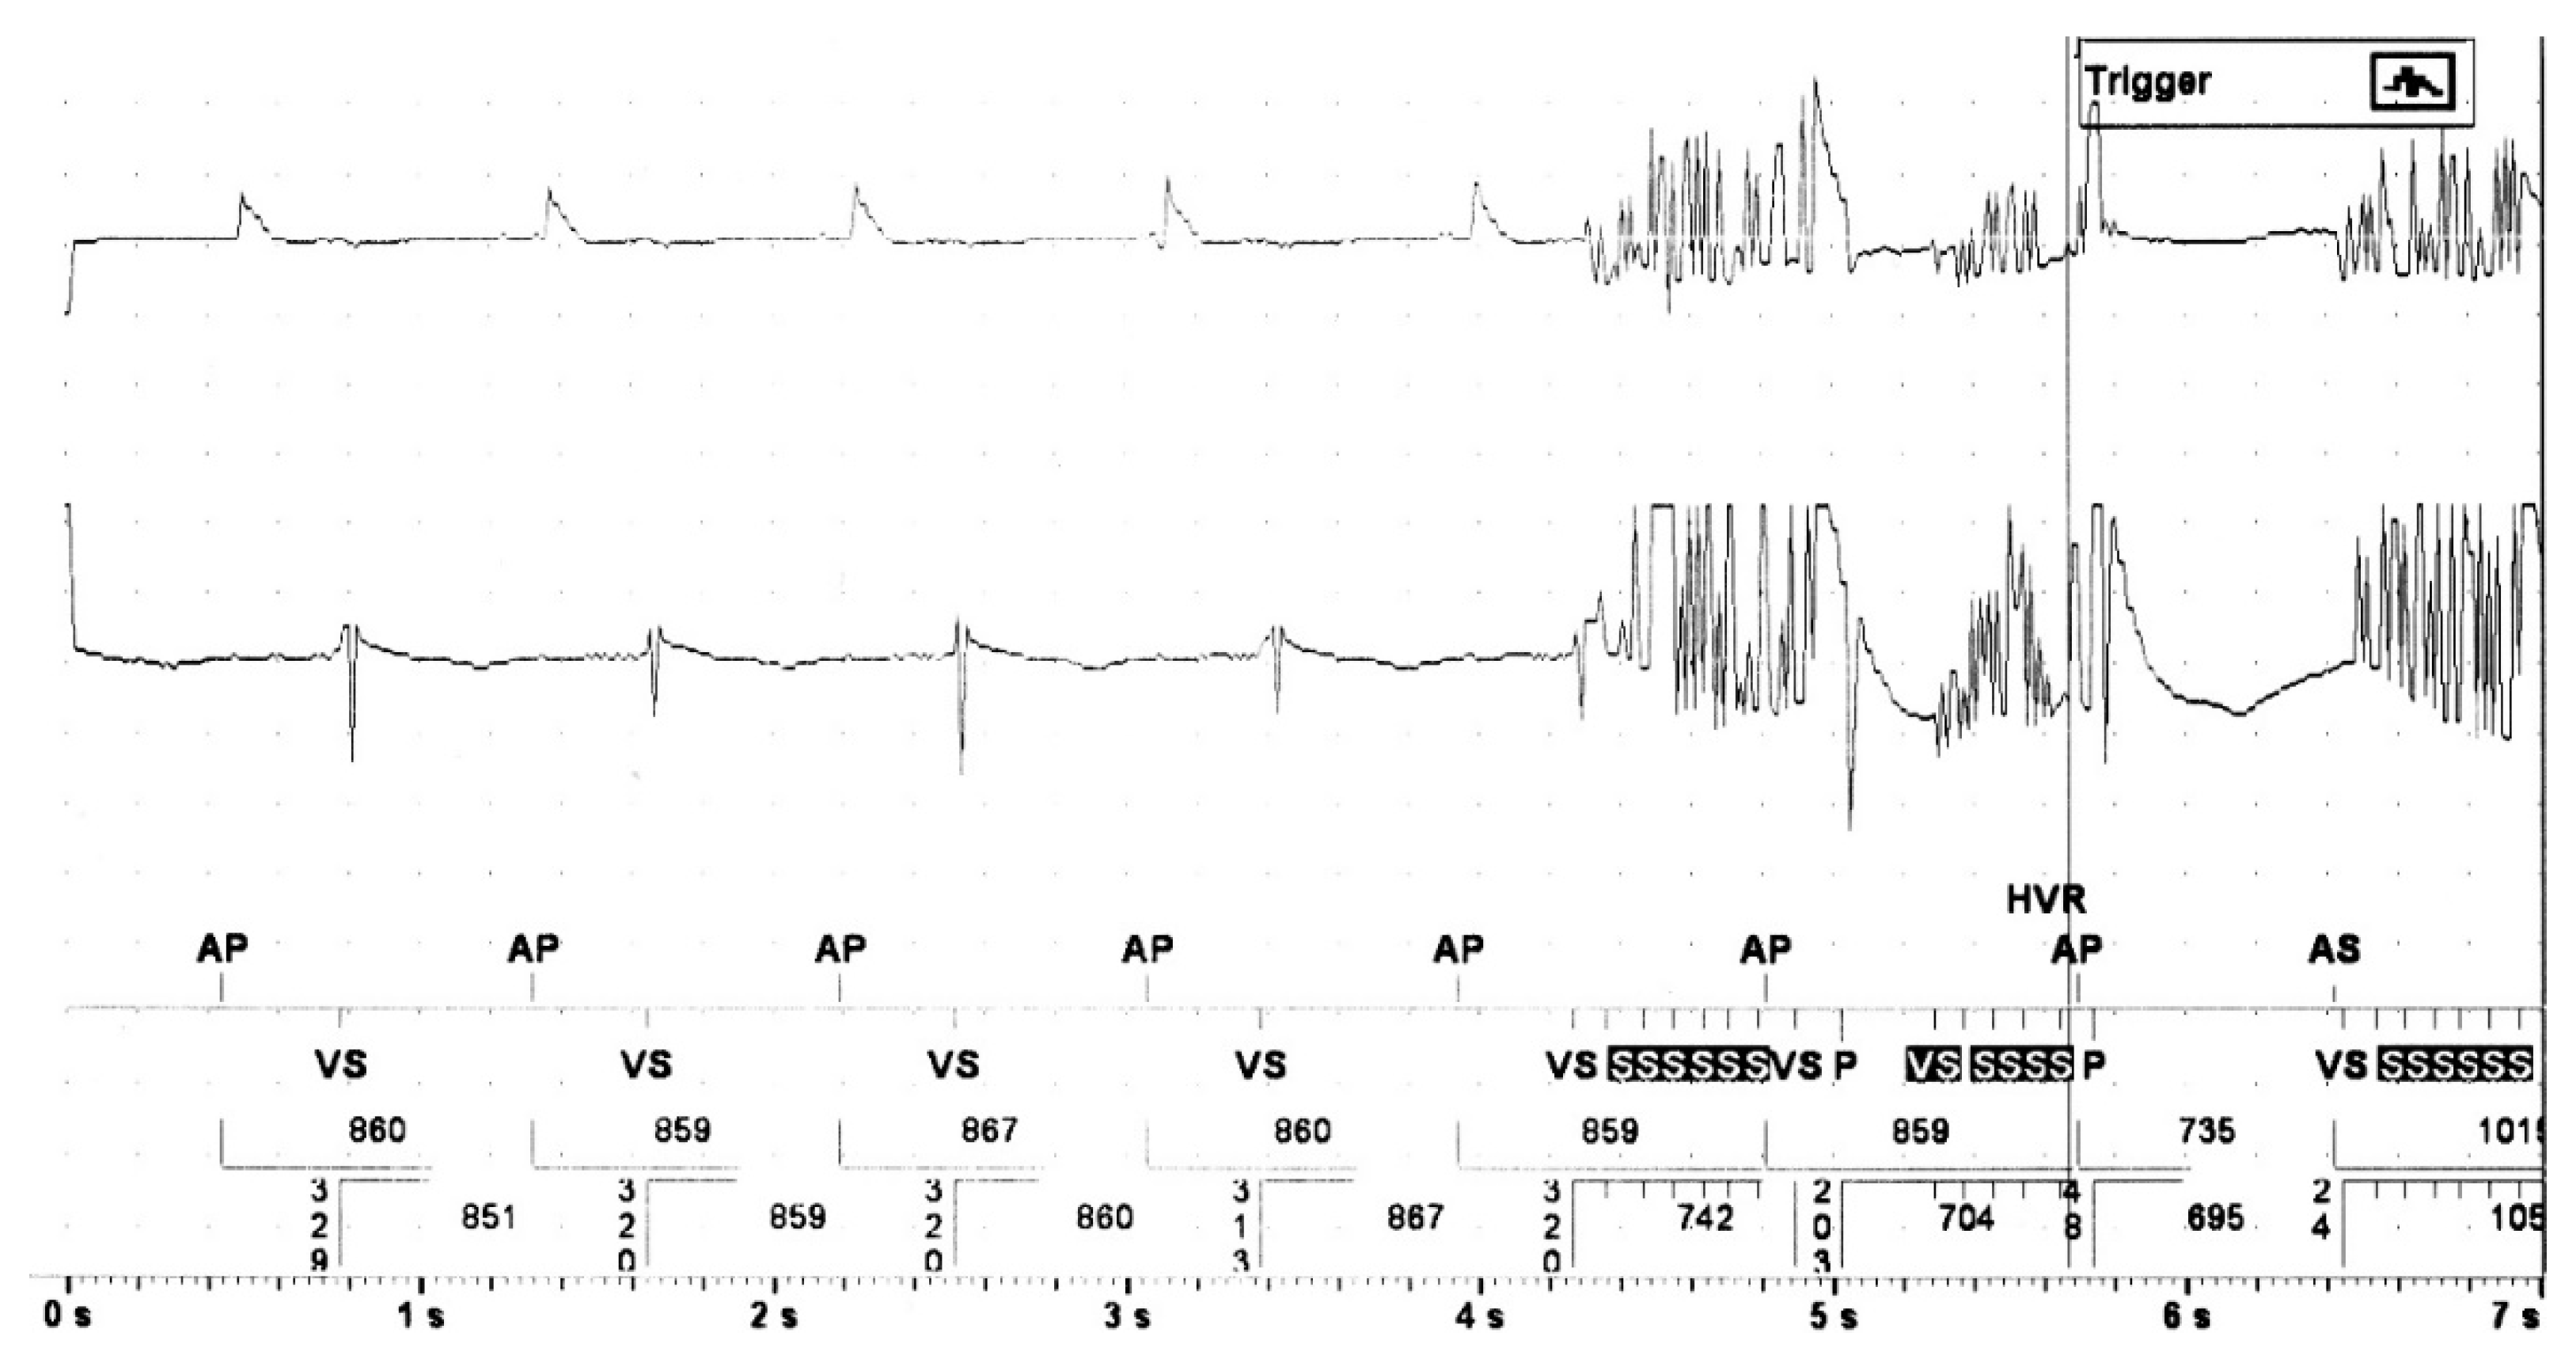

Patients with cardiac implantable electronic devices (CIED) undergoing non-device associated surgery require an individual peri-interventional management, in particular with regard to possible side effects of electromagnetic interferences (EMI, Figure 1) [1].

Figure 1.

Example of electromagnetic interference due to monopolar electrocautery. Both the atrial (fist line) and ventricular EGM (middle line) show pulsed artefacts in a patient with implanted conventional dual chamber pacemaker undergoing repair of the ascending aorta.